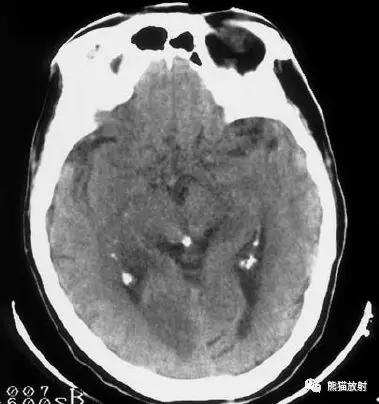

左侧大脑中动脉血栓形成(箭头)—— “大脑中动脉高密度征”,发病后不久行CT检查:相应的血管区域见缺血性病变。